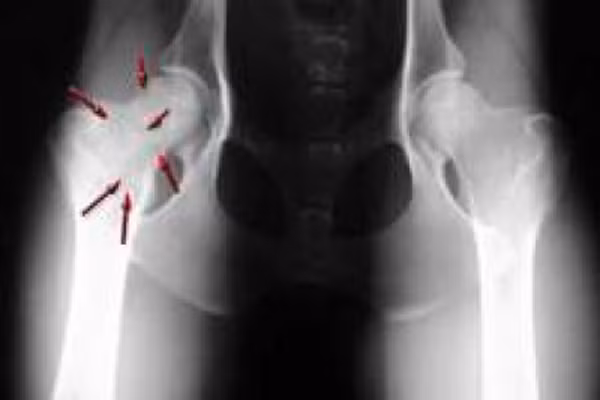

(Kiến Thức) - Trong tất cả các bệnh lí về xương thì ung thư xương là bệnh nguy hiểm nhất, bạn hãy chú ý đến những dấu hiệu đau sau.

Đau ở xương. Là triệu chứng phổ biến nhất của bệnh ung thư xương. Cơn đau sẽ không cố định thời gian trong ngày và dường như tồi tệ hơn vào ban đêm. Đặc biệt là, bạn sẽ bị đau nhức, khập khiễng khi đi lại.

Nếu khối u nằm ở các khớp thì bạn sẽ khó cử động, điều này gây khó khăn cho sự di chuyển như, khối u nằm ở chân thì khó đi lại, u nằm ở tay khiến bạn khó cầm nắm và cảm thấy đau nhoi nhói như có vật gì nằm dưới da vậy.